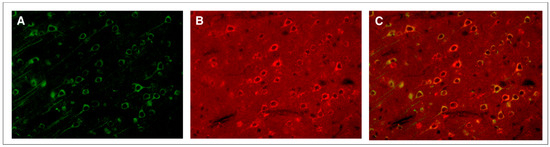

- Donkin, J.J.; Nimmo, A.J.; Cernak, I.; Blumbergs, P.C.; Vink, R. Substance P is associated with the development of brain edema and functional deficits after traumatic brain injury. J. Cereb. Blood Flow. Metab. 2009, 29, 1388–1398. [Google Scholar] [CrossRef]